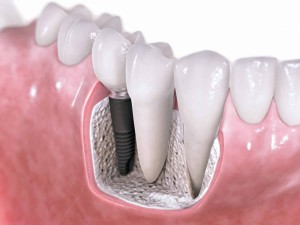

Цель имплантологического лечения — не воткнуть импланты так, чтобы они прижились, а создание надёжной и долговечной опоры под планируемую ортопедическую конструкцию.

В настоящий момент производители выпускают линейки имплантов, предназначенных для установки в лунку только что удаленного зуба. Они отличаются крупной агрессивной резьбой, назначение которой – обеспечить качественную стабилизацию импланта в условиях лунки только что удаленного зуба.